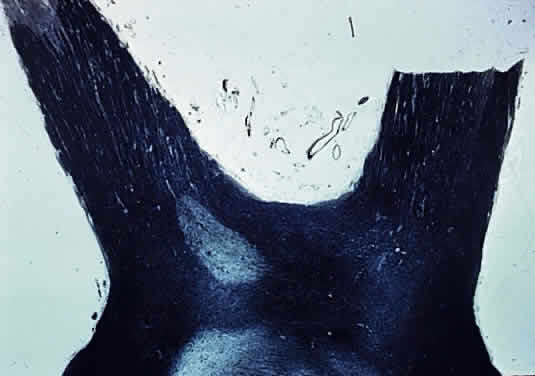

The optic stalk develops from the optic vesicle at about the seventh week of gestation; from this is derived the optic vesicle, which matures into the globe. The optic nerve is continuous with the optic tract (Fig. 1). The number of axons in the human optic nerve rapidly increases during early embryogenesis to reach a peak of about 3 million during the second trimester, after which loss of fibers occurs until about 1 million fibers remain at birth.1 The diameter of the optic nerve increases throughout embryogenesis—from about 0.15 mm at the ninth week of gestation until full term, when it averages 2.7 mm.2 Myelination by oligodendroglial cells begins near the optic chiasm at about the 30th week of gestation, extends distally as far as the laminar cribrosa, and is complete at or soon after birth (Fig. 2).2

Fig. 2. Myelination of normal adult optic nerve up to lamina cribrosa (longitudinal section Luxol Fast Blue stain).